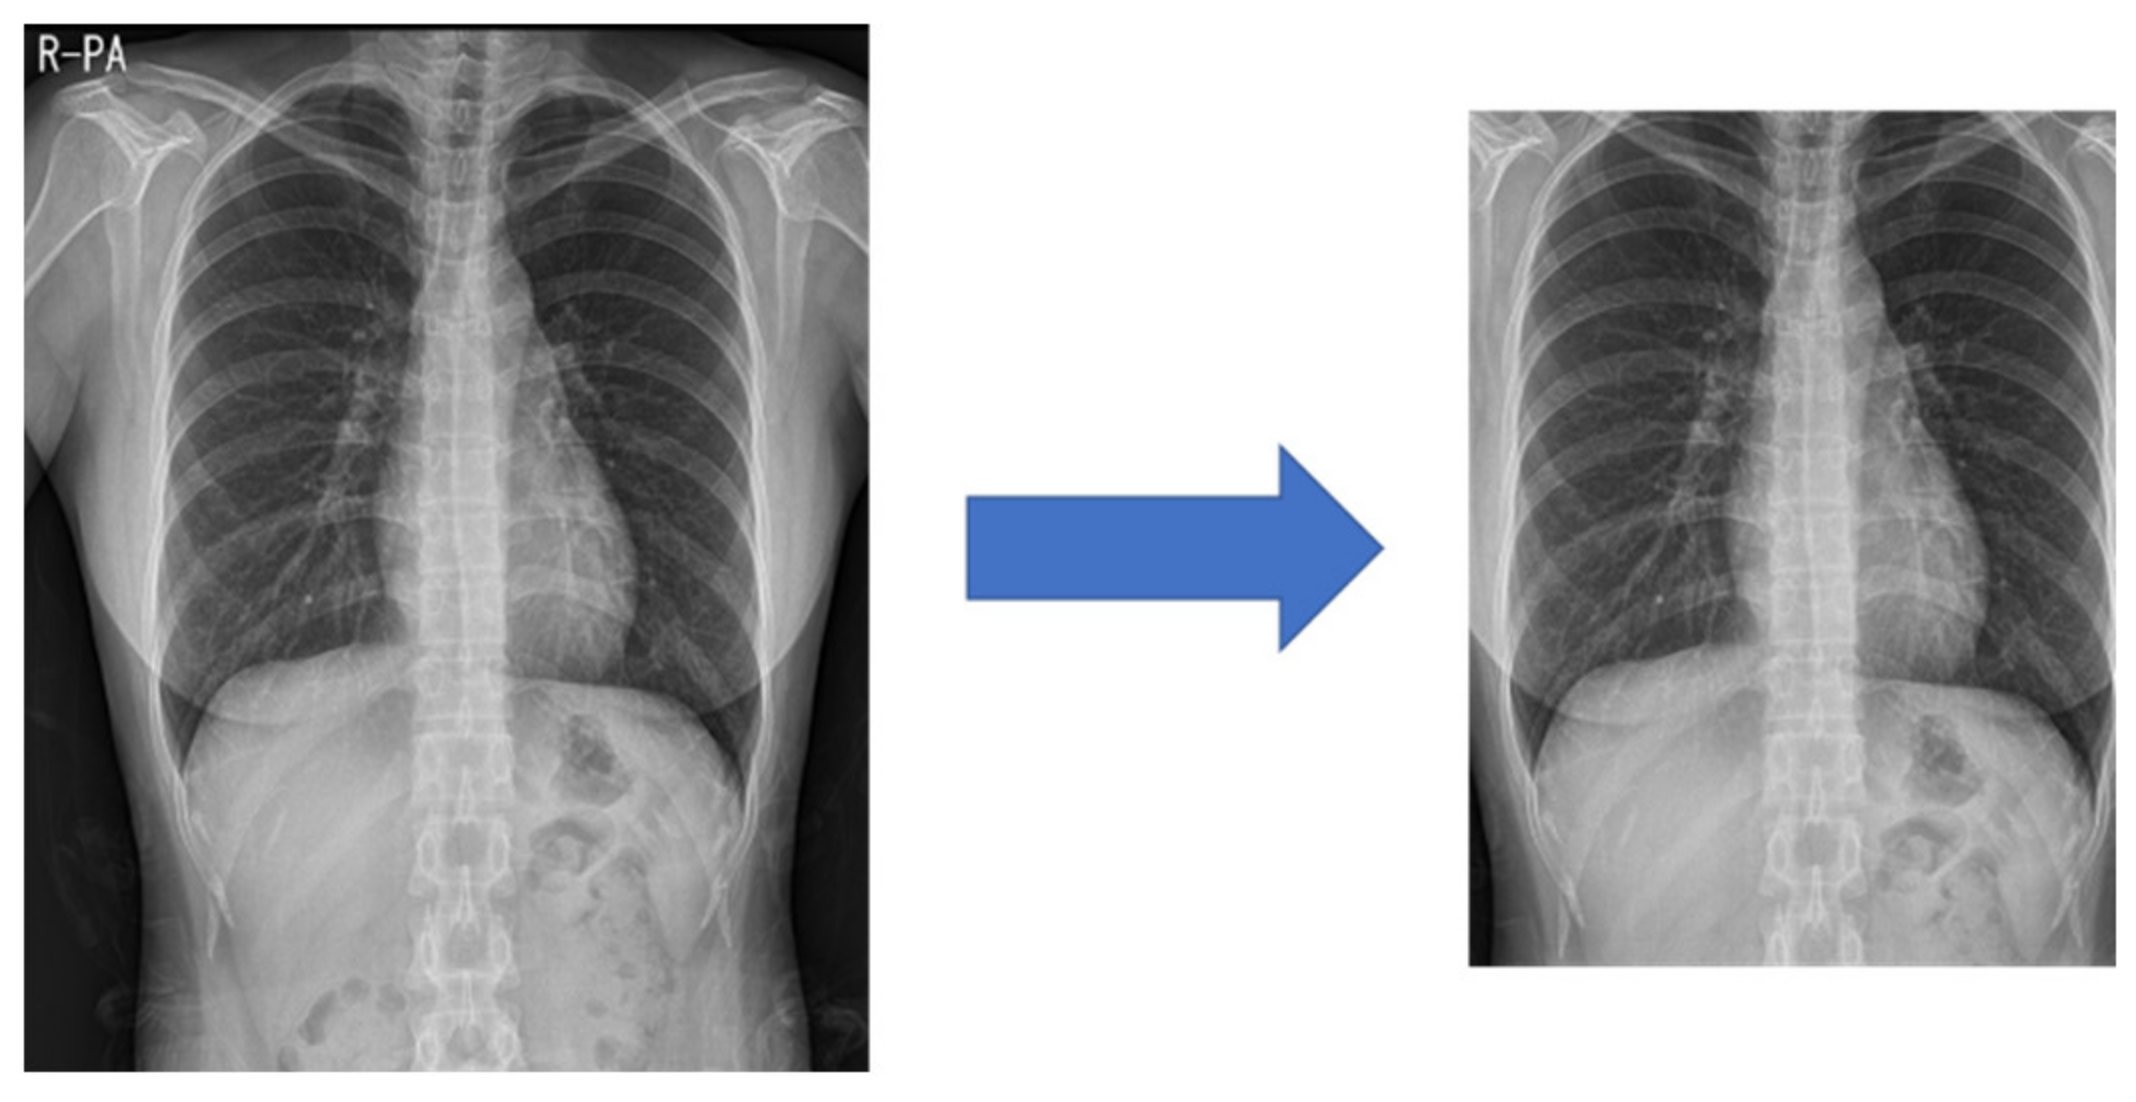

Figure 15 shows the training graph of the model that predicted Normal, Pneumonia, Pneumothorax, and Tuberculosis by learning 51,866 de-identified images provided by Soonchunhyang University Hospital, Cheonan. The performance was measured with a single model to which both the proposed preprocessing and multi GAP were applied, and the performance of the test set was measured in the epoch that had the highest validation accuracy performance. Figure 16 shows examples of correct predictions and incorrect predictions by classes.

As a result of learning all 60 epochs, the 35 epochs showed the highest performance, and the validation performance of the 35 epochs was shown in Table 12. As a result of measuring the performance of the test set, the test performance and inference time are shown in Table 13 and Table 14.

Figure 16. Correct predictions and incorrect predictions by classes.